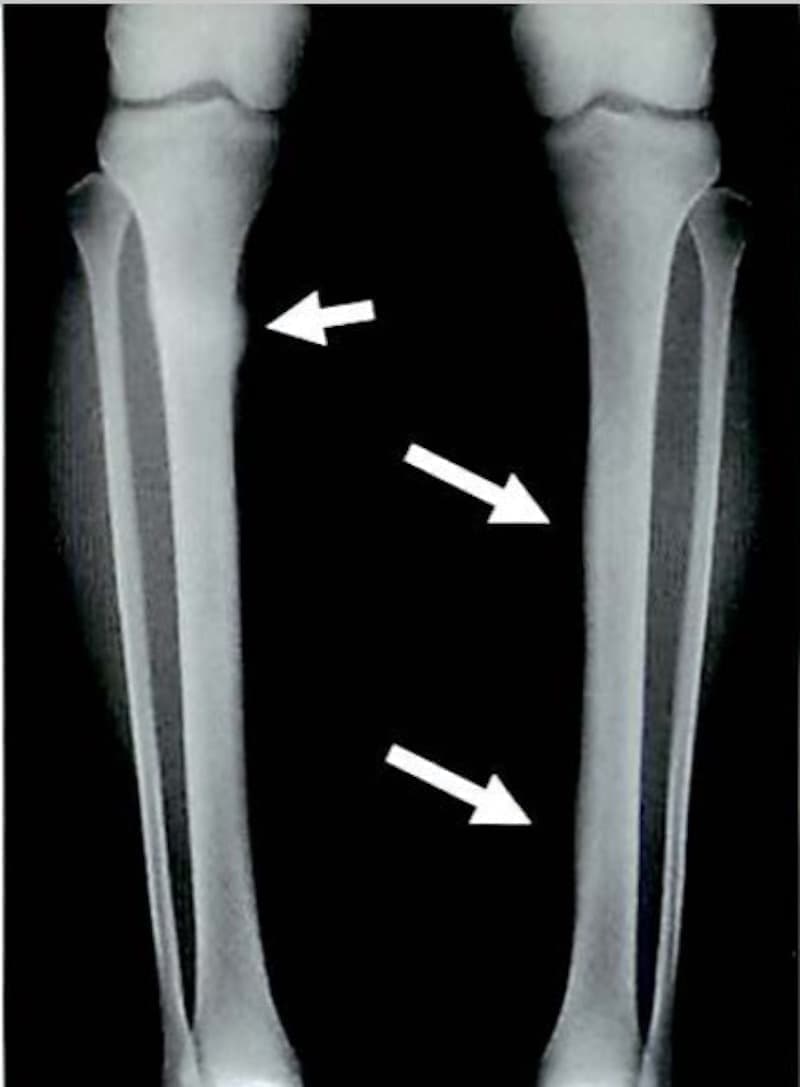

疲労骨折は健常な骨において同一部位に外力が繰り返されることによって

骨が疲弊し起こる骨折です。

突然起きる骨折とは異なり、ジャンプやダッシュなどの通常のスポーツにより

繰り返される外力が骨に微細な骨折(顕微鏡レベルで確認できる)を引き起こします。

初期は骨がストレスに反応して骨吸収像を呈し、経過するに従い骨吸収と骨新生が

複雑に並存した状態に進んでいきます。

つまり繰り返す弱い力により骨に小さな骨折が引き起こされ、

その状態が慢性的に続くことで大きな骨折に発展するということです。

スポーツの種類により

肋骨(剣道)、頚椎(ゴルフ)、尺骨(バレー、ソフトボール)恥骨(卓球)

脛骨(長距離走、走高跳など)、腓骨(長距離走)、中足骨(短距離走)

などが疲労骨折の好発部位となります。

※ Monthly orthopaedicsから画像抜粋